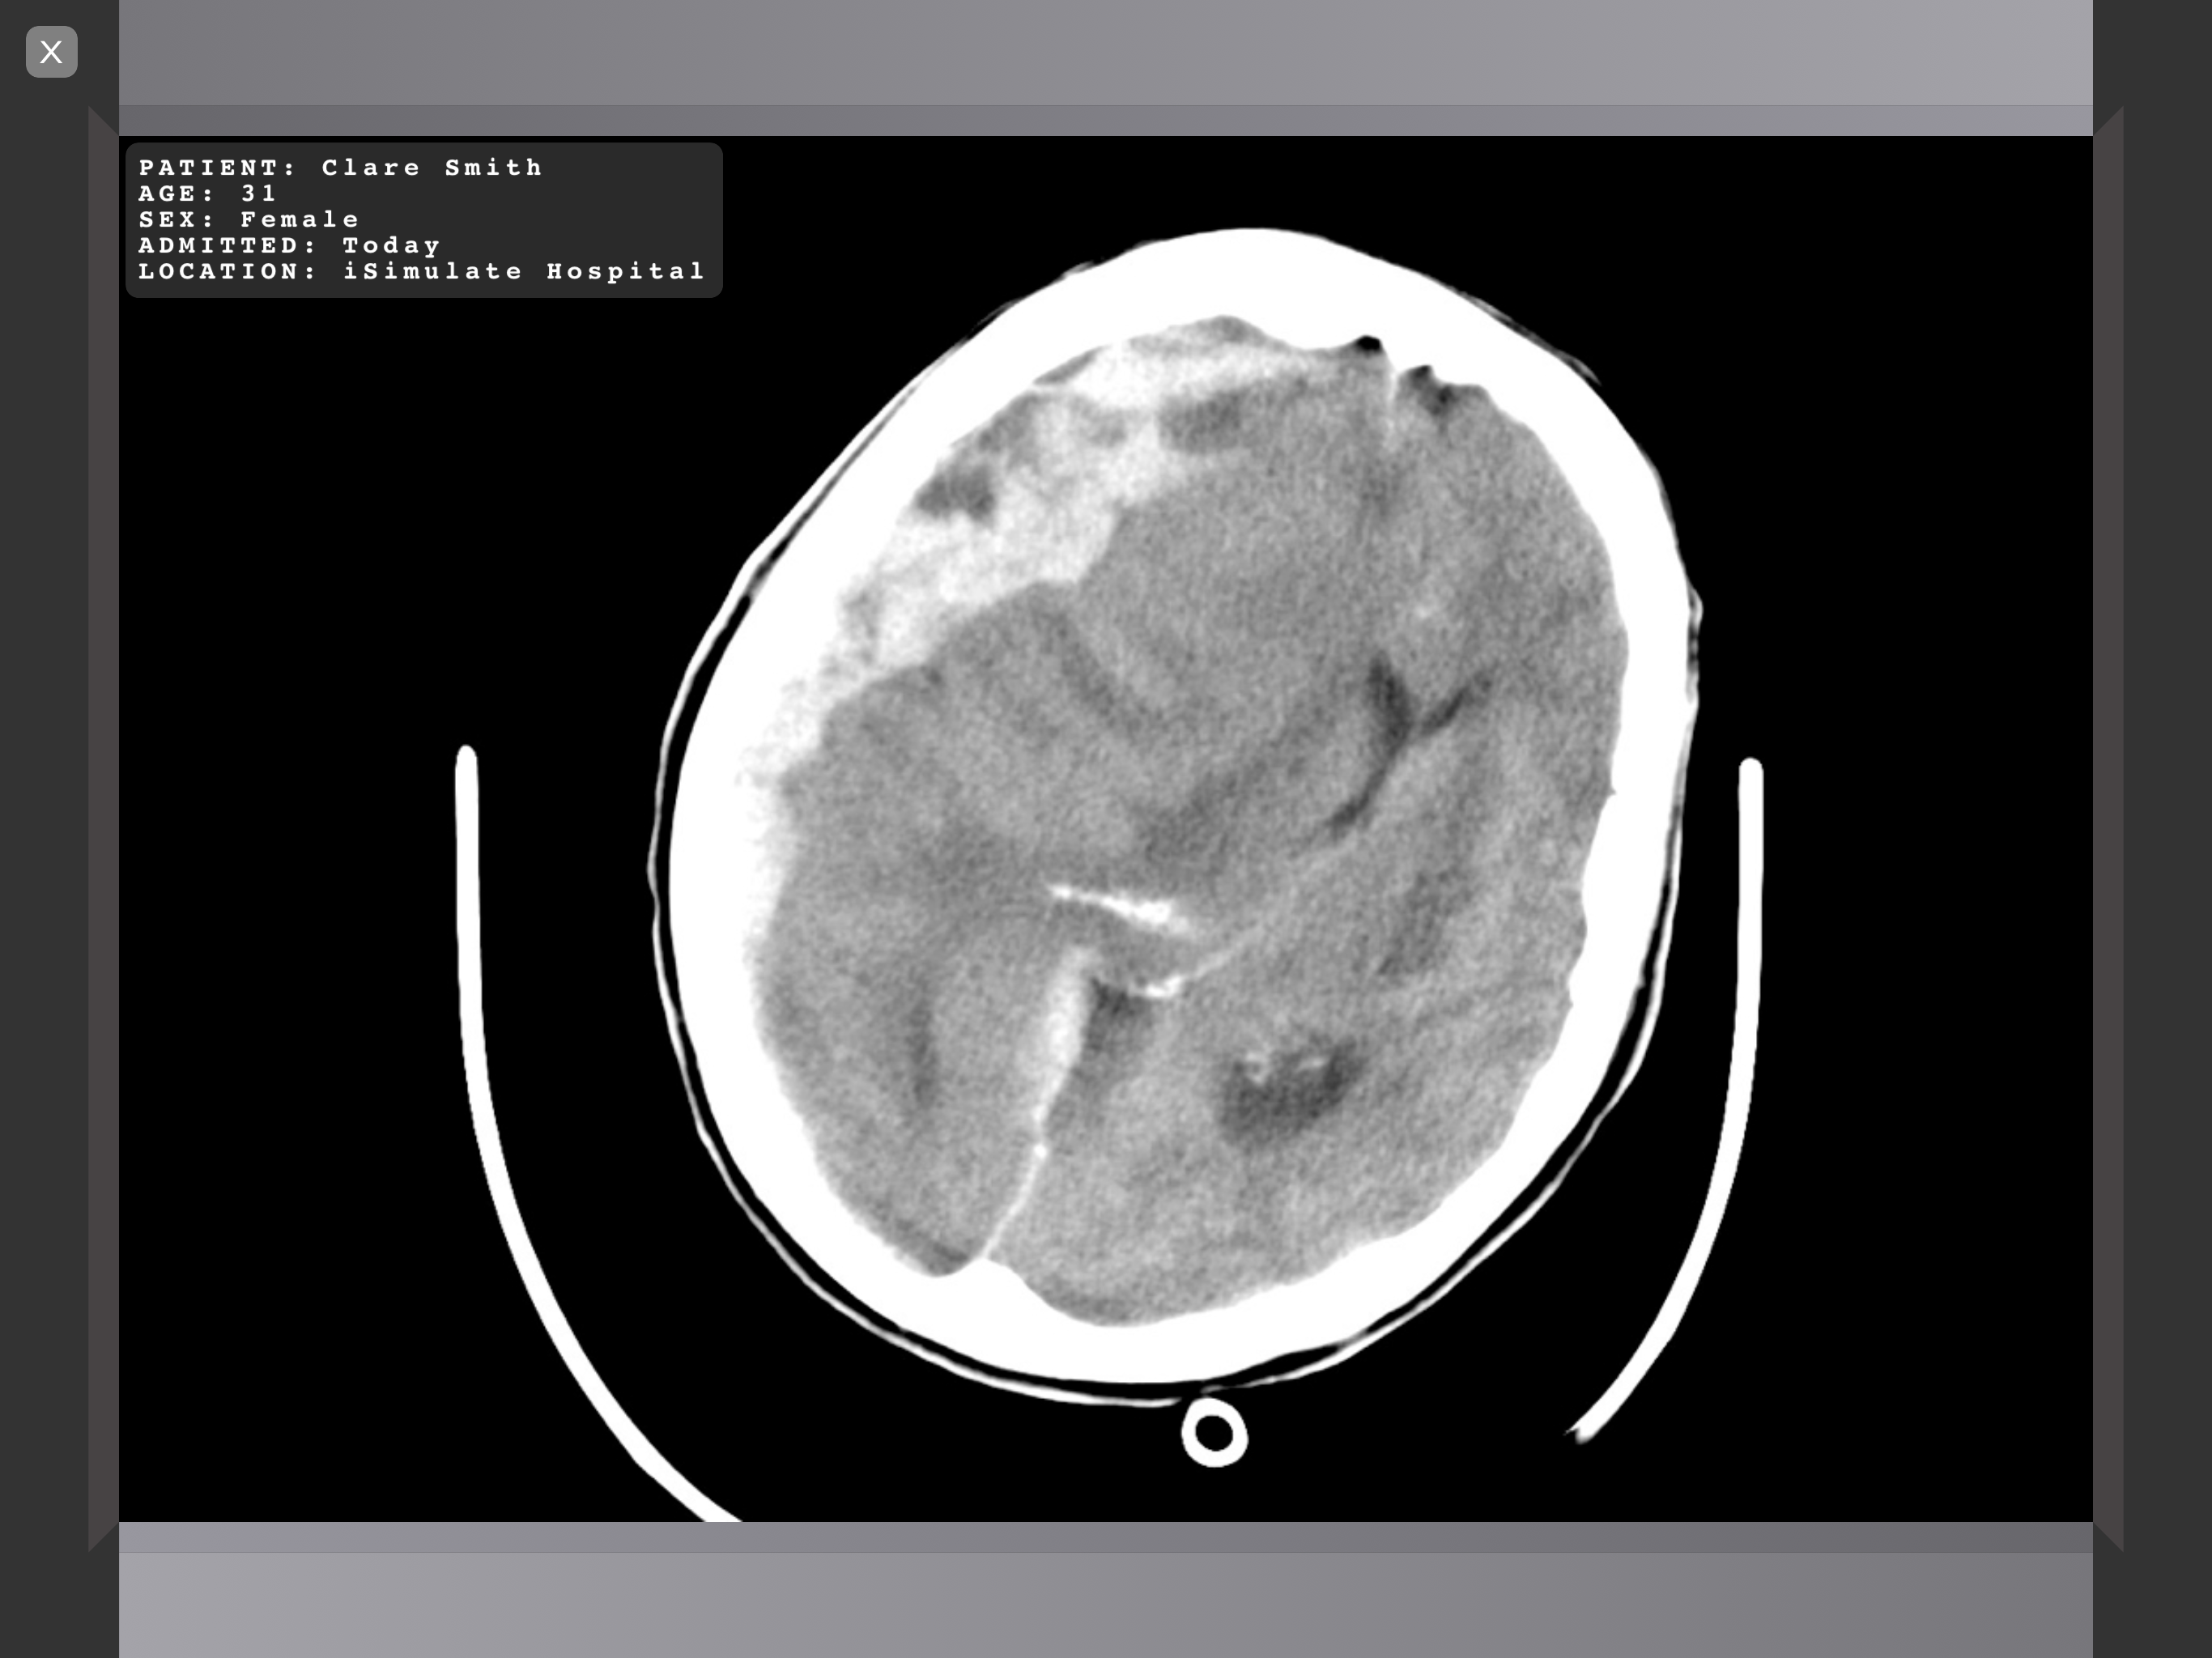

下の画像例のようにモニターへ表示される場合、Scenario Information(シナリオ情報)がメディア上にテキストで追加されます。

General(一般), Ultrasound(超音波), Radiography(X線撮影) 分類のメディアが対象です。

Radiography(X線撮影)